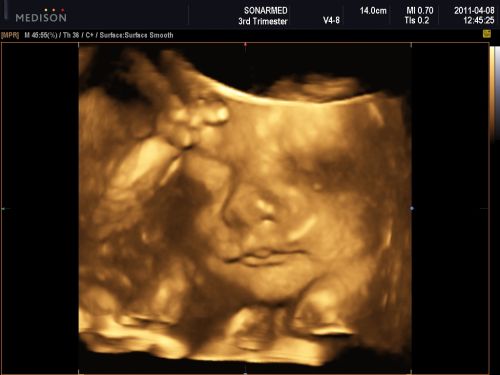

Amúgy nemrég voltam uh-on, és csücsült a baba, kezdek ideges lenni, mert a 18. héten voltam utoljára, akkor mondták lánynak, most meg ugye nem látszott, és mindent lányosat szereztünk be, a szoba is az, szóval most először várom a köv. uh-ot, ami a 36.-on lesz.

A nagylányom pedig összeszervált egy streptococcust, torokgyuszi formájában, itthon van még egy hetet, és nyűglődik, mert még pár napig nem engedem ugrálni, meg játszóterezni. A babának meg lassan örülnöm kell, ha nem lesz két feje és hat lábujja, tekintve, hogy az összes létező veszélyes fertőzést hazahordták a gyerekeim (emlékeztek, volt bárányhimlő is...).Azt mondták uh-on, hogy minden oké, de azért én már várom, hogy megnézzem, átszámoljam....